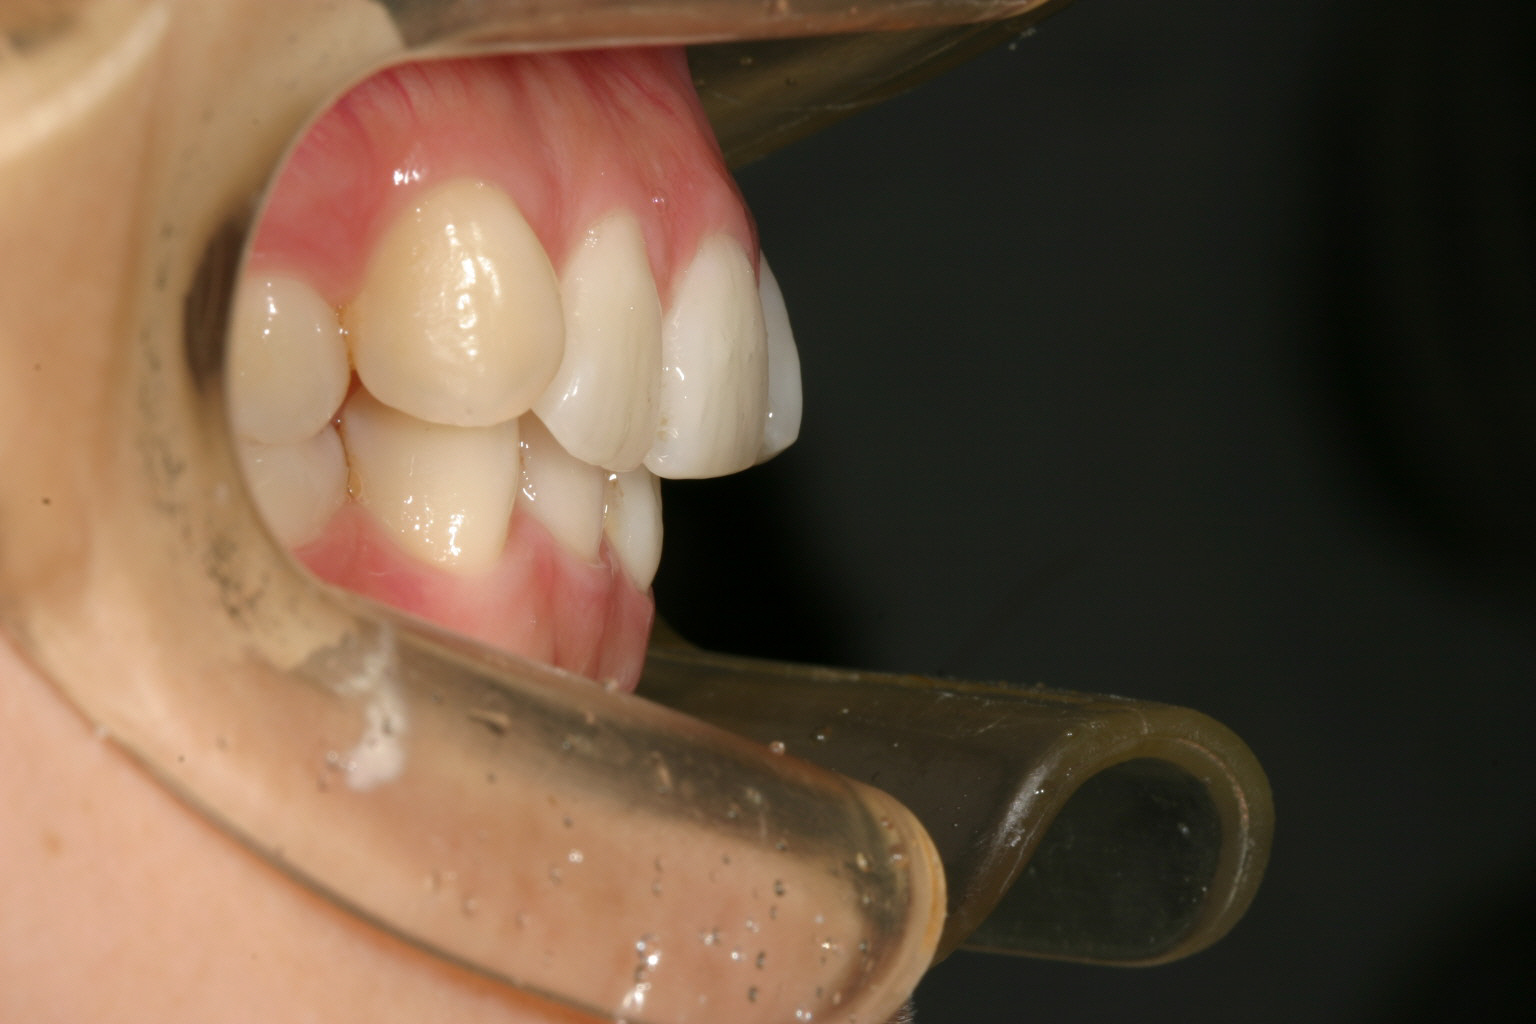

少し上顎出ていますね~

オーバージェットを綺麗に改善しました。